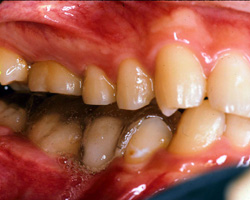

(症例)患者様、93年7月初診 当時16歳男性

(主訴)左側顎関節症、頭痛、右側腰痛、右足後部の疼痛

(診査診断、治療方針) BBO診断の結果

1)頭位が右にスライドし左へ傾斜している。

2)上顎歯列の左右差そのものに問題がある。

3)顎関節負担の前歯型になっている。

| 写真−術前 | |

初めに上顎の歯列を上顎基準まで削台します。これは下顎骨は好ましい機能を有する上骨に沿って移動していくものでBBOで は、上顎の平面(咬合平菌可の見直しは調整時には毎回必要な操作であります。写真1) 2)は上顎のシーネと下顎BBOのスプリントです。頭部を、脳頭蓋、顔血眼蓋、下顎体と三つに大別して各々の正中や位置を確認すると左右差があり、位置偏 位が判断できます。このことは、頭蓋骨(特に側頭骨や蝶形骨)下顎体や頚椎にさえ歪みがあることを示しているのです。そこでこれらの歪みをとることが先決 であり、そうすることによって少なくとも現状より良好な結果を生むことになるのです。その時のワックスバイトは噛み切らないバイトを採得することが大切で す。もしバイトを噛み切ってしまうと特定の歯の歯根膜センサーが動き顎運動を制限してしまうため上下顎の歯牙が一次接触をした部位を支点として下顎骨が回 転偏位をおこしてしまいます。